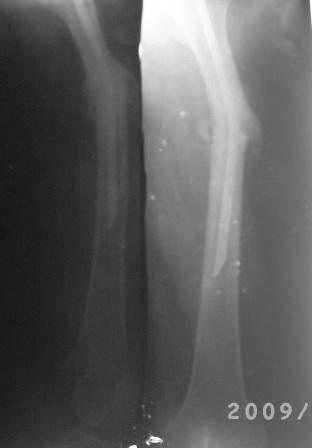

[Ortho] Искривление и/м штифта

12.02.09г б-ная оперирована: з/остеоклазия (без особого труда-

видимо тугой ложный сустав) коррекция деформации, удаление штифта

из надвертельной обл, рассверление канала гибкими развертками,

реостеосинтез блокируюшим гвоздем Д-11мм.

Но я впервые почувствовал такую сильно ОСТЕОПОРОТИЧНУЮ кость, что

блокируюшие винты проваливаются внутрь кости, что винты можно

ввести без сверления кости, и что винты провинчиваются холостую,

т.е. не стабильно.

P.S. Снимки не качественные, извиняюсь! последний снимок ЭРГА, два снимка объединил.